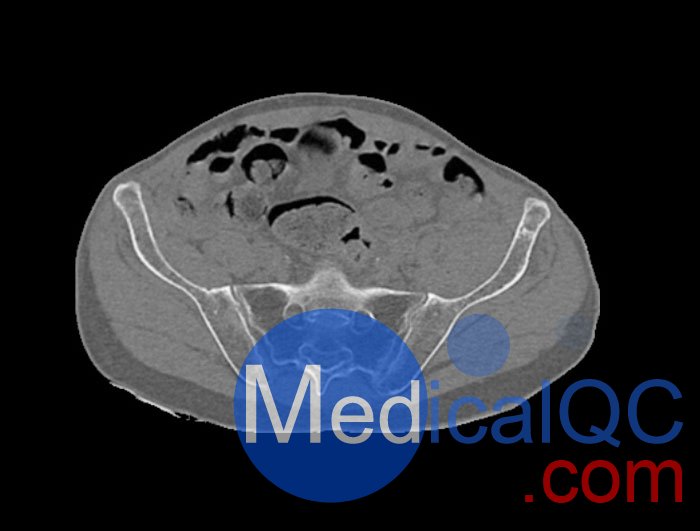

WEK54-01股骨頸骨折骨盆模型,WEK54-01骨盆模體詳細介紹:

WEK54-01股骨頸骨折骨盆模型,WEK54-01骨盆模體模擬沒有靜脈造影劑的骨盆(天然)。它覆蓋了整個骨盆,直到第五腰椎。

左側股骨頸移位骨折。

該模型可用于 CT(包括 CBCT)和射線照相,以評估和優(yōu)化成像性能和后處理應用,包括支持 AI 的應用。它也適用于培訓目的。

WEK54-01股骨頸骨折骨盆模型,WEK54-01骨盆模體提供了對軟組織和骨組織的詳細而逼真的模擬。空隙中填充著約-160HU的纖維素-聚合物復合材料。

WEK54-01股骨頸骨折骨盆模型,WEK54-01骨盆模體成像效果圖: